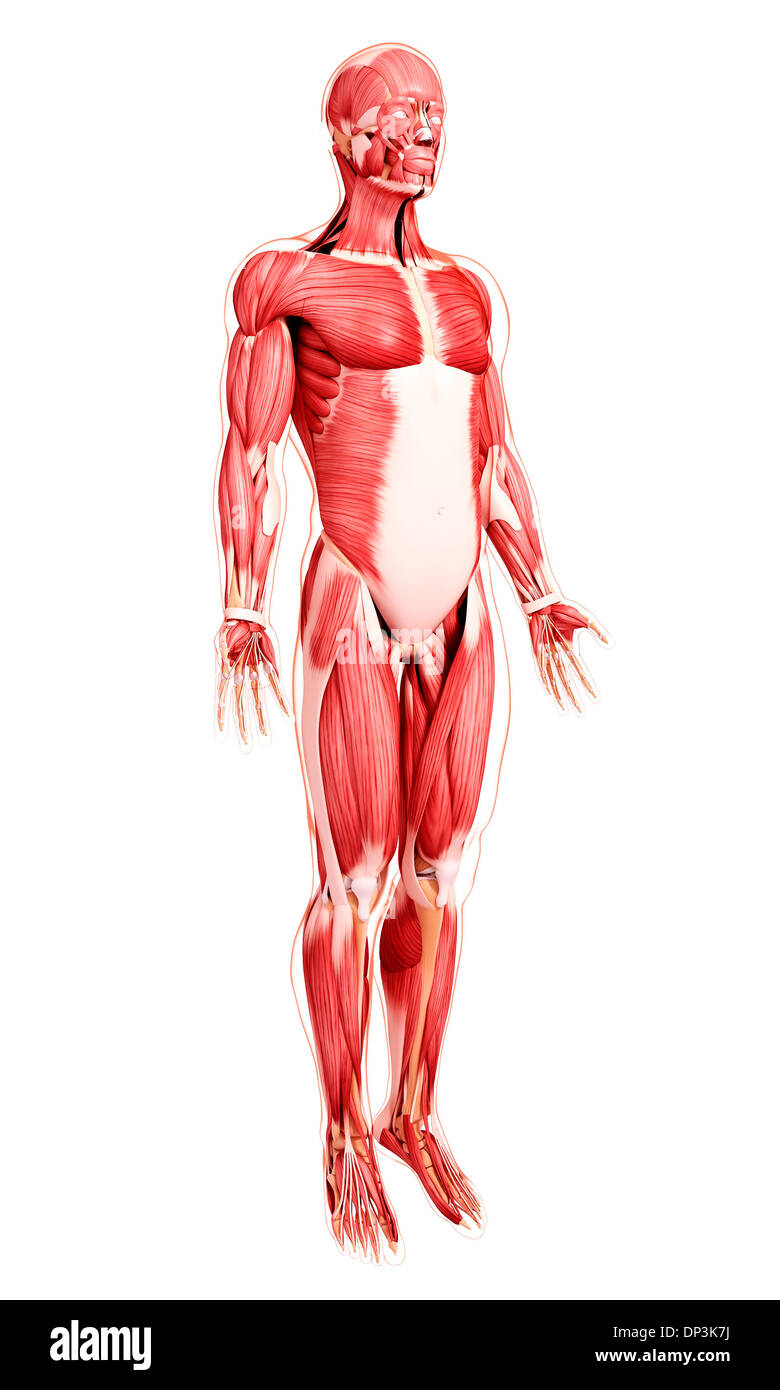

Les droits de l'Anatomy, artwork Banque D'Imageshttps://www.alamyimages.fr/image-license-details/?v=1https://www.alamyimages.fr/les-droits-de-l-anatomy-artwork-image65234502.html

Les droits de l'Anatomy, artwork Banque D'Imageshttps://www.alamyimages.fr/image-license-details/?v=1https://www.alamyimages.fr/les-droits-de-l-anatomy-artwork-image65234502.htmlRFDP3K7J–Les droits de l'Anatomy, artwork

Musculature, artwork Banque D'Imageshttps://www.alamyimages.fr/image-license-details/?v=1https://www.alamyimages.fr/musculature-artwork-image65229644.html

Musculature, artwork Banque D'Imageshttps://www.alamyimages.fr/image-license-details/?v=1https://www.alamyimages.fr/musculature-artwork-image65229644.htmlRFDP3D24–Musculature, artwork

Musculature, artwork Banque D'Imageshttps://www.alamyimages.fr/image-license-details/?v=1https://www.alamyimages.fr/musculature-artwork-image65226679.html

Musculature, artwork Banque D'Imageshttps://www.alamyimages.fr/image-license-details/?v=1https://www.alamyimages.fr/musculature-artwork-image65226679.htmlRFDP3987–Musculature, artwork

Musculature, artwork Banque D'Imageshttps://www.alamyimages.fr/image-license-details/?v=1https://www.alamyimages.fr/musculature-artwork-image65241101.html

Musculature, artwork Banque D'Imageshttps://www.alamyimages.fr/image-license-details/?v=1https://www.alamyimages.fr/musculature-artwork-image65241101.htmlRFDP3YK9–Musculature, artwork